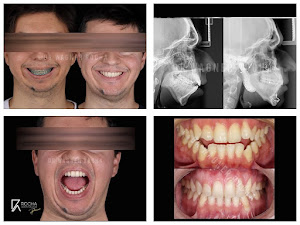

💥Observe nesse caso a importância de fazermos um diagnóstico precoce, aproveitando a fase de crescimento ósseo no adolescente. De uma forma simples m… Publicado em: 26 de maio de 2025